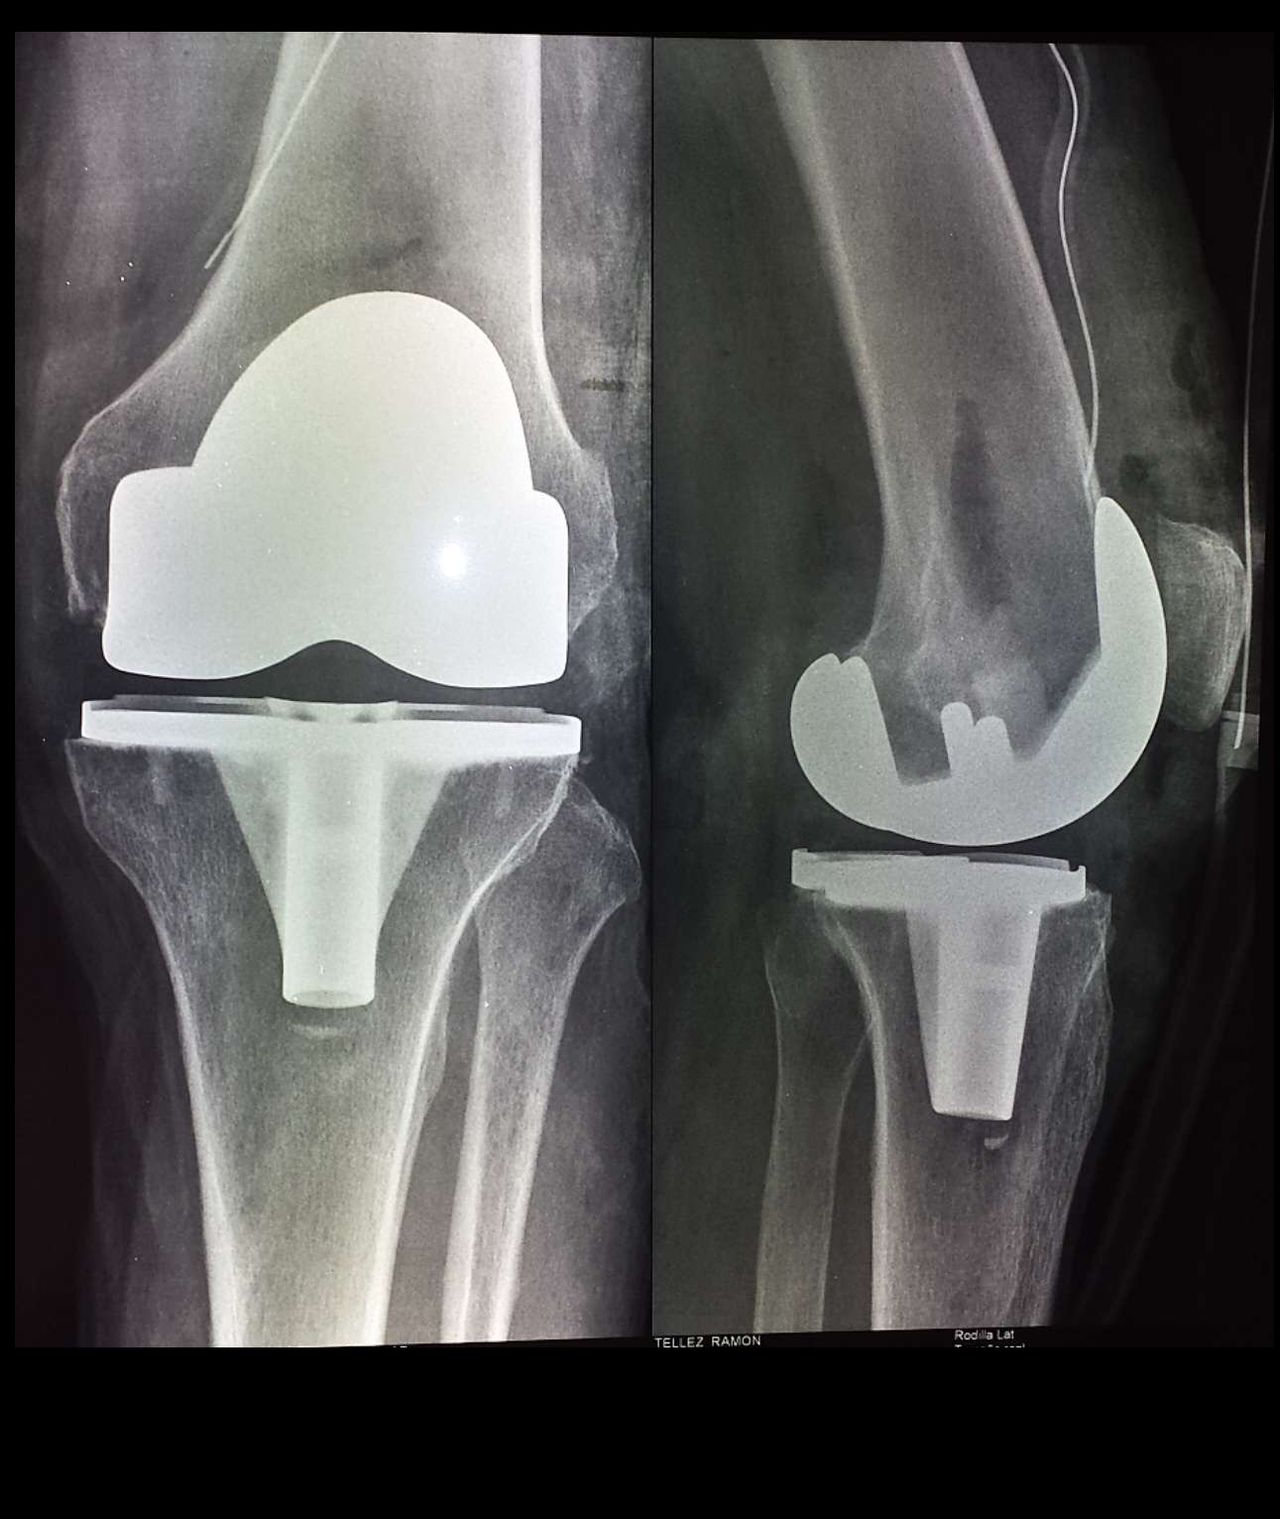

• Prótesis de rodilla

Artroplastia rodilla con prótesis total

Cuando el desgaste articular de la rodilla, no permite tratamientos de preservación y rescate articular, y la calidad de vida del paciente está afectada, existe un procedimiento que ayuda a mejorar esta calidad de vida, ayuda a quitar el dolor, consiste en el reemplazo de la articulación de la rodilla, ayudando a la alineación de la extremidad, pero sobre todo ayuda al paciente a una vida sin dolor.